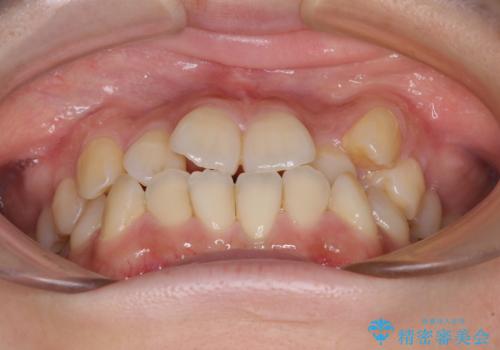

- 八重歯や前歯の捻転とクロスバイトが気になり、インビザラインによる矯正治療を希望して来院された患者様です。

上顎側切歯(上の真ん中から2番目の歯)が舌側転位している場合、無理して動かそうとすると歯髄壊死を起こすリスクが高い印象があります。

インビザライン単体でも治療は可能ですが、安全策としてインビザラインで歯列を移動する前に上顎前歯をワイヤー矯正で整え、その後上下歯列をインビザラインにて矯正治療を行うこととしました。